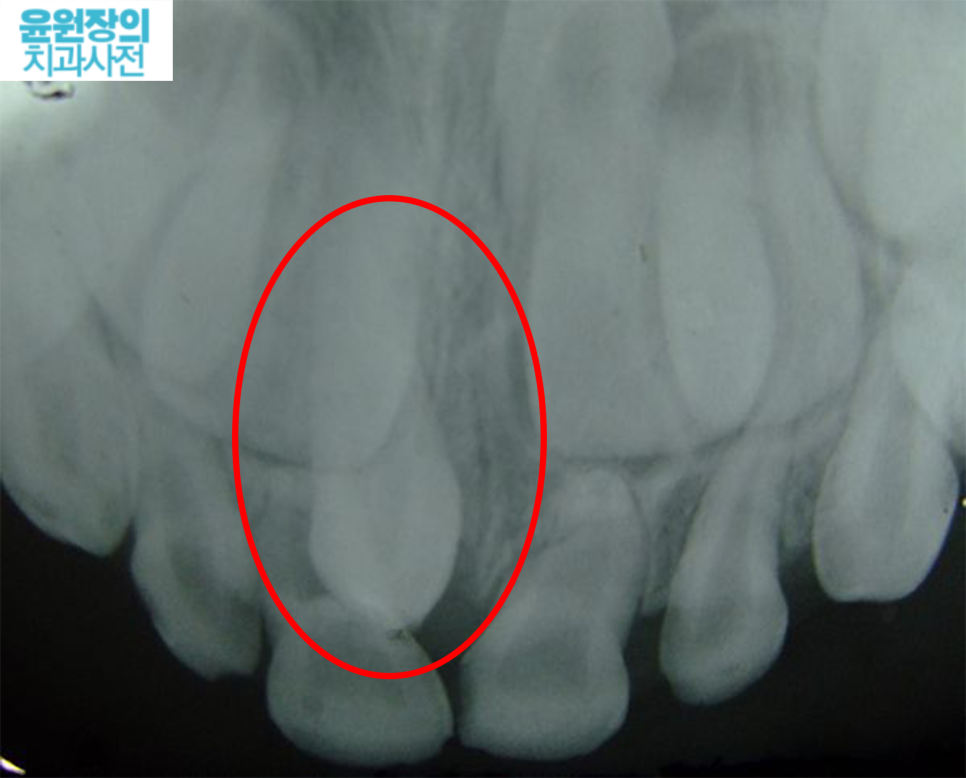

단 뽑기 전에, 우선적으로 엑스레이를 통해서 과잉치의 방향과 위치를 확인해야 합니다.

과잉치는 굉장히 특이해서 흔히 우리가 생각하는 치아처럼 반듯하게 생기지 않습니다.

방향이 위쪽을 향할 수도 있구요, 오른쪽 왼쪽 제각각입니다.

심지어 위치도 다양합니다. 다행히 많이 내려와있는 경우도 있지만요, 코에 가깝게 올라가서 발견되는 경우도 많습니다.